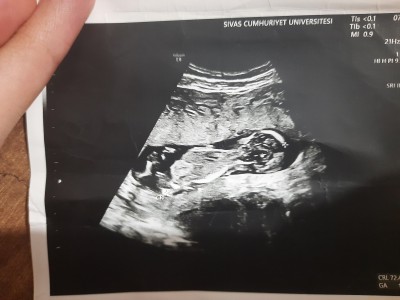

Ultrasona göre cinsiyet tahmini yapabilecek varmı resimli13+3

Cinsiyet tahmini anlayan varmı

Erkek gibimsi bacim dr bisey demedimi

Canim doktor gördü sanki ama gülerek birdahaki gelmene dedi söyleyeyim bilerek sanki demedi bir daha da insalllah 1 aya gidicem merak ettim baya

Sadece sallıyorum canm içimden geçen erkek bebek :) sağlıklı olsun da Allah gönlüne göre versin

Bence kızın olacak :)